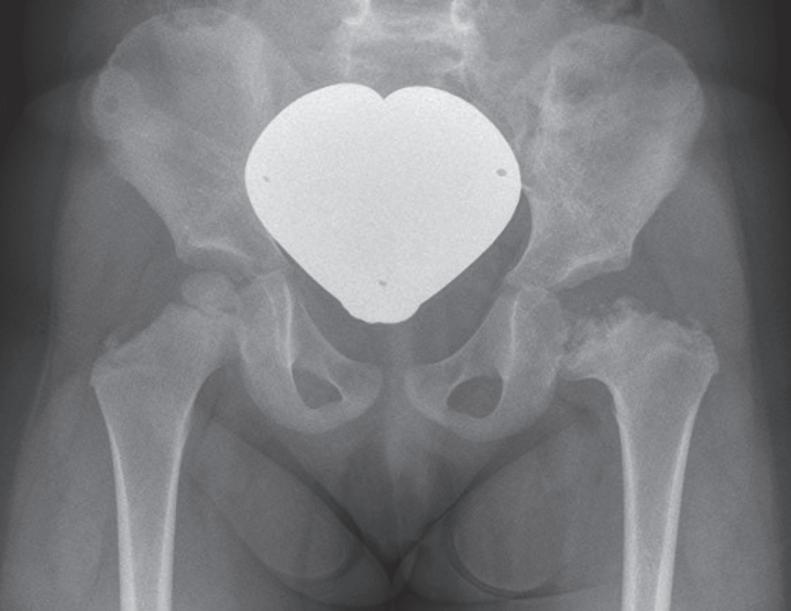

Uma radiografia é necessária para cada articulação do quadril previamente tratada para descartar necrose da cabeça femoral ou um novo distúrbio de maturação do quadril em um momento posterior, por exemplo, aos 2 anos de idade, antes de começar a escola, antes da puberdade e após a conclusão do crescimento (▶ Fig. 1.1).

Fig. 1.1 Formação de uma necrose da cabeça femoral à esquerda após redução fechada de uma luxação do quadril do lado esquerdo diagnosticada pela primeira vez com quase 6 meses de idade.

Com uma incidência de 2 a 4%, os distúrbios da maturação do quadril estão entre as malformações mais comuns do sistema musculoesquelético. A displasia do quadril é a causa mais comum de coxartrose precoce em todo o mundo, com a consequência da artroplastia precoce do quadril na idade do jovem adulto [18]. Para os afetados, a doença geralmente está associada a muito sofrimento ( ▶ Fig. 1.3).

Fig. 1.3 Consequências tardias de uma luxação do quadril.

a Coxa vara após necrose da cabeça femoral.

b Artrose na displasia do teto acetabular.

c Luxação inveterada do quadril.